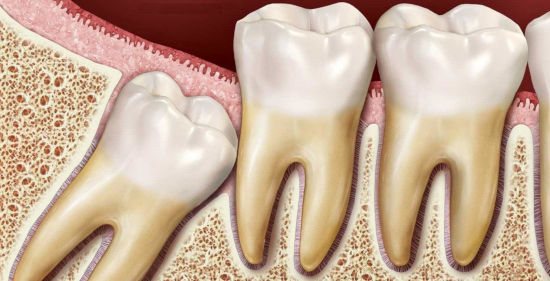

Прорезывание последнего в ряду моляра, который называют зубом мудрости, очень часто приносит человеку много сложностей.

Появление в челюстном ряду этого элемента зачастую происходит позже, нежели всех остальных зубов, а также влечет за собой различные проблемы.

Капюшон над зубом мудрости – это образование, сформированное из десенных слизистых тканей, находящихся над прорезывающейся единицей. Они образуют плотный, но не герметичный покров.

Во время прорезывания зуба мудрости, его зачастую покрывает слизистая оболочка дёсенной ткани, которая не является полностью герметичной, а сохраняет промежуток между собой и растущим моляром. Стоматологи называют этого тканевое образование капюшоном.